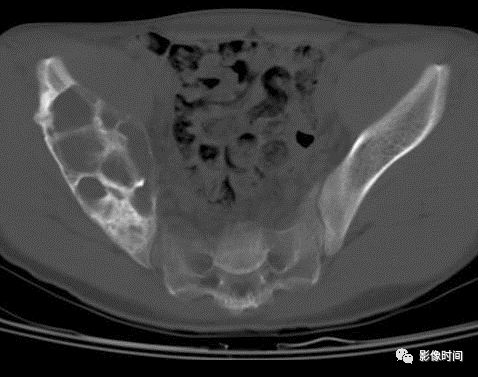

(二)营养不良性钙化   营养不良性钙化为局部钙盐代谢异常所致的钙化。X 线平片和 CT 表现为无结构的不规则形致密影。

良性肿瘤常见于骨内脂肪瘤(图 39),恶性骨肿瘤则常见于 PNET(图 40)和未分化多形性肉瘤。

图 39  营养不良性钙化:骨内脂肪瘤

图 40  营养不良性钙化:PNET